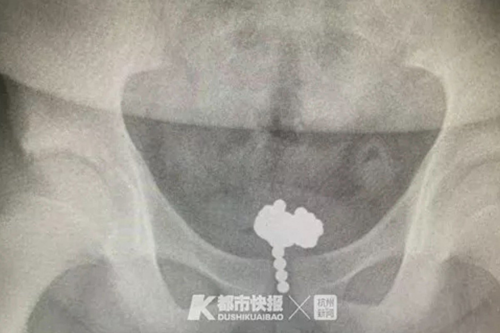

70 viên bi nam châm trong bàng quang bé trai 11 tuổi